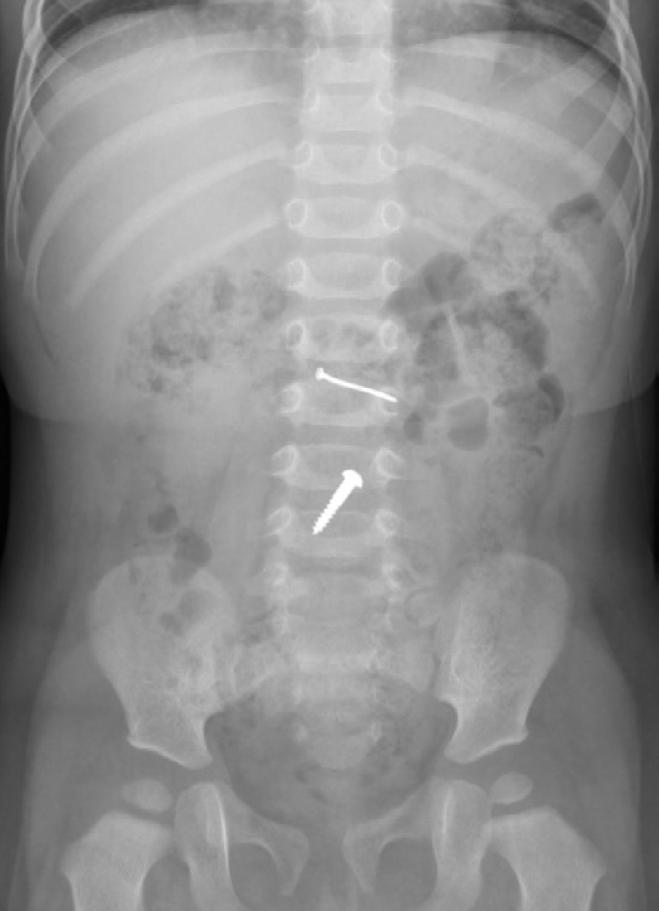

Dans notre cohorte, les objets les plus souvent ingérés étaient les pièces de monnaie (n=153 ; 25 % des cas), puis les jouets (n=69 ; 10,8 %), les piles boutons (n=69 ; 10,8 %), les bijoux (n=39 ; 6,2 %), les aimants (n=38 ; 6,2 %) et divers autres objets : clous, vis, roches, etc. (n=251)6 .

5INGESTION D'AIMANTS

MULTIPLES 6 LONGUE VIS DE 5 CM DANS

L’ANTRE INGÉRÉE PAR UN

GARÇON DE 5 ANS

Dans ces situations, leur retrait s’impose lorsqu’ils se trouvent dans l’œsophage ou dans l’estomac. Si le corps étranger est déjà dans l’intestin grêle, un retour à domicile avec surveillance parentale est possible. Il faut néanmoins rester vigilant devant des symptômes tels les vomissements qui seraient le signe d’une sténose liée à une compression de l’intestin grêle (figure 5).

D’autres objets

De multiples autres objets peuvent être ingérés par les enfants: des roches, des billes, des clous, des vis, des punaises de bureau, des morceaux de verre, du métal et autres objets pointus ou arrondis. La conduite à tenir pour les objets métalliques est le

retraitlorsqu’ils restent logés sans progression dans l’œsophage depuis plusieurs heures ou s’ils sont tranchants ou pointus. Dans la localisation gastrique, le caractère tranchant ou pointu et la grande taille (plus de 4 cm) sont aussi des facteurs conduisant au retrait endoscopique. L’exemple d’une longue vis visualisée dans l’antre gastrique lors de l’endoscopie est présenté à la figure 6 (voir page 51).